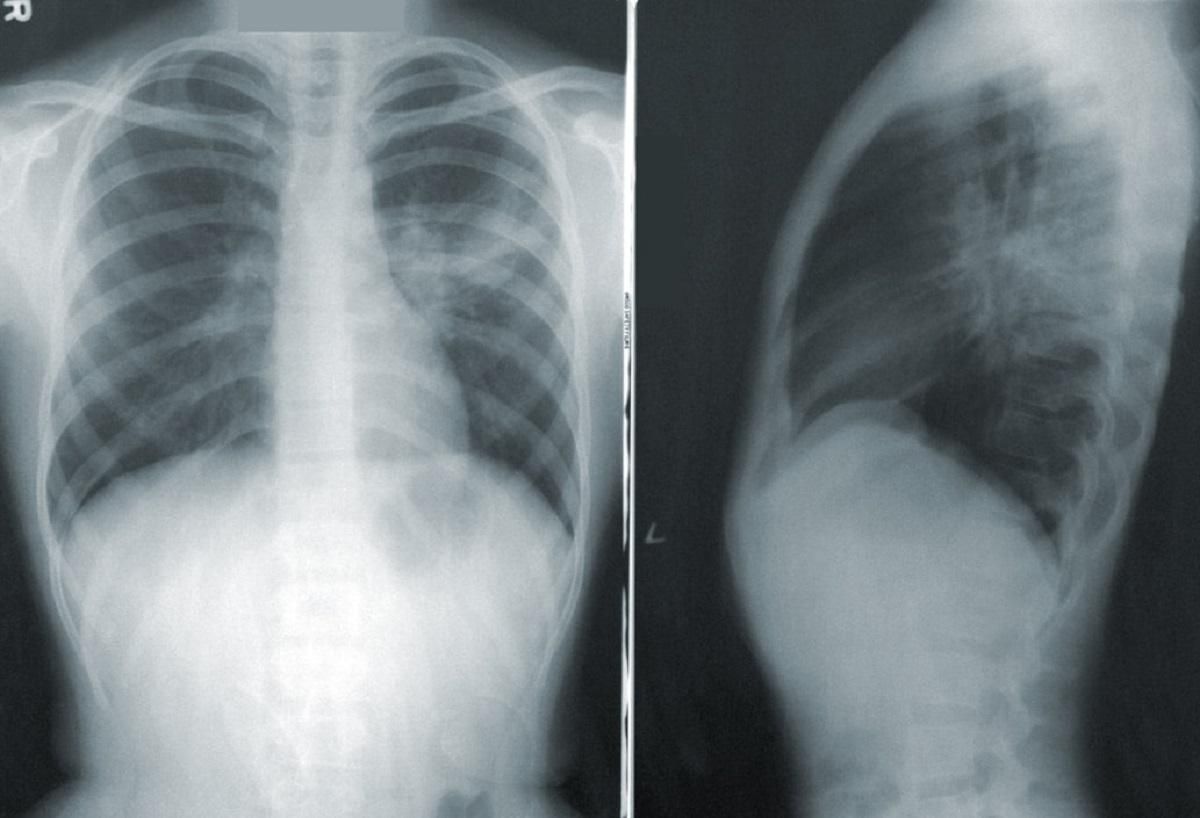

Хворий 3 тижні страждав від сухого кашлю, лихоманки та задишки. Під час госпіталізації на його рентгенівських знімках медики виявили колапс легені.

У пацієнта діагностували напружений пневмоторакс, який виникає тоді, коли повітря затримується в плевральній порожнині під тиском. Такий стан може виникати від важкої травми грудної клітки, перелому ребра, внаслідок дайвінгу чи прогулянок на великій висоті.

З огляду на історію хвороби, обстеження та рентгенологічні результати, цілком ймовірно, що цей пацієнт страждав на COVID-19, який потім ускладнився пневмотораксом,

Чоловікові надали екстрену допомогу із введенням дихальної трубки та провели дренаж легені.